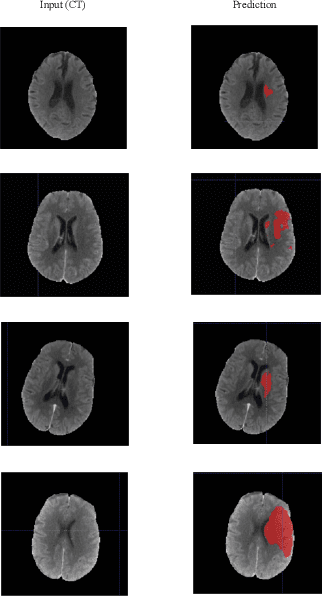

Abstract:Ischemic stroke occurs through a blockage of clogged blood vessels supplying blood to the brain. Segmentation of the stroke lesion is vital to improve diagnosis, outcome assessment and treatment planning. In this work, we propose a segmentation model with adversarial learning for ischemic lesion segmentation. We adopt U-Net with skip connection and dropout as segmentation baseline network and a fully connected network (FCN) as discriminator network. Discriminator network consists of 5 convolution layers followed by leaky-ReLU and an upsampling layer to rescale the output to the size of the input map. Training a segmentation network along with an adversarial network can detect and correct higher order inconsistencies between the segmentation maps produced by ground-truth and the Segmentor. We exploit three modalities (CT, DPWI, CBF) of acute computed tomography (CT) perfusion data provided in ISLES 2018 (Ischemic Stroke Lesion Segmentation) for ischemic lesion segmentation. Our model has achieved dice accuracy of 42.10% with the cross-validation of training and 39% with the testing data.